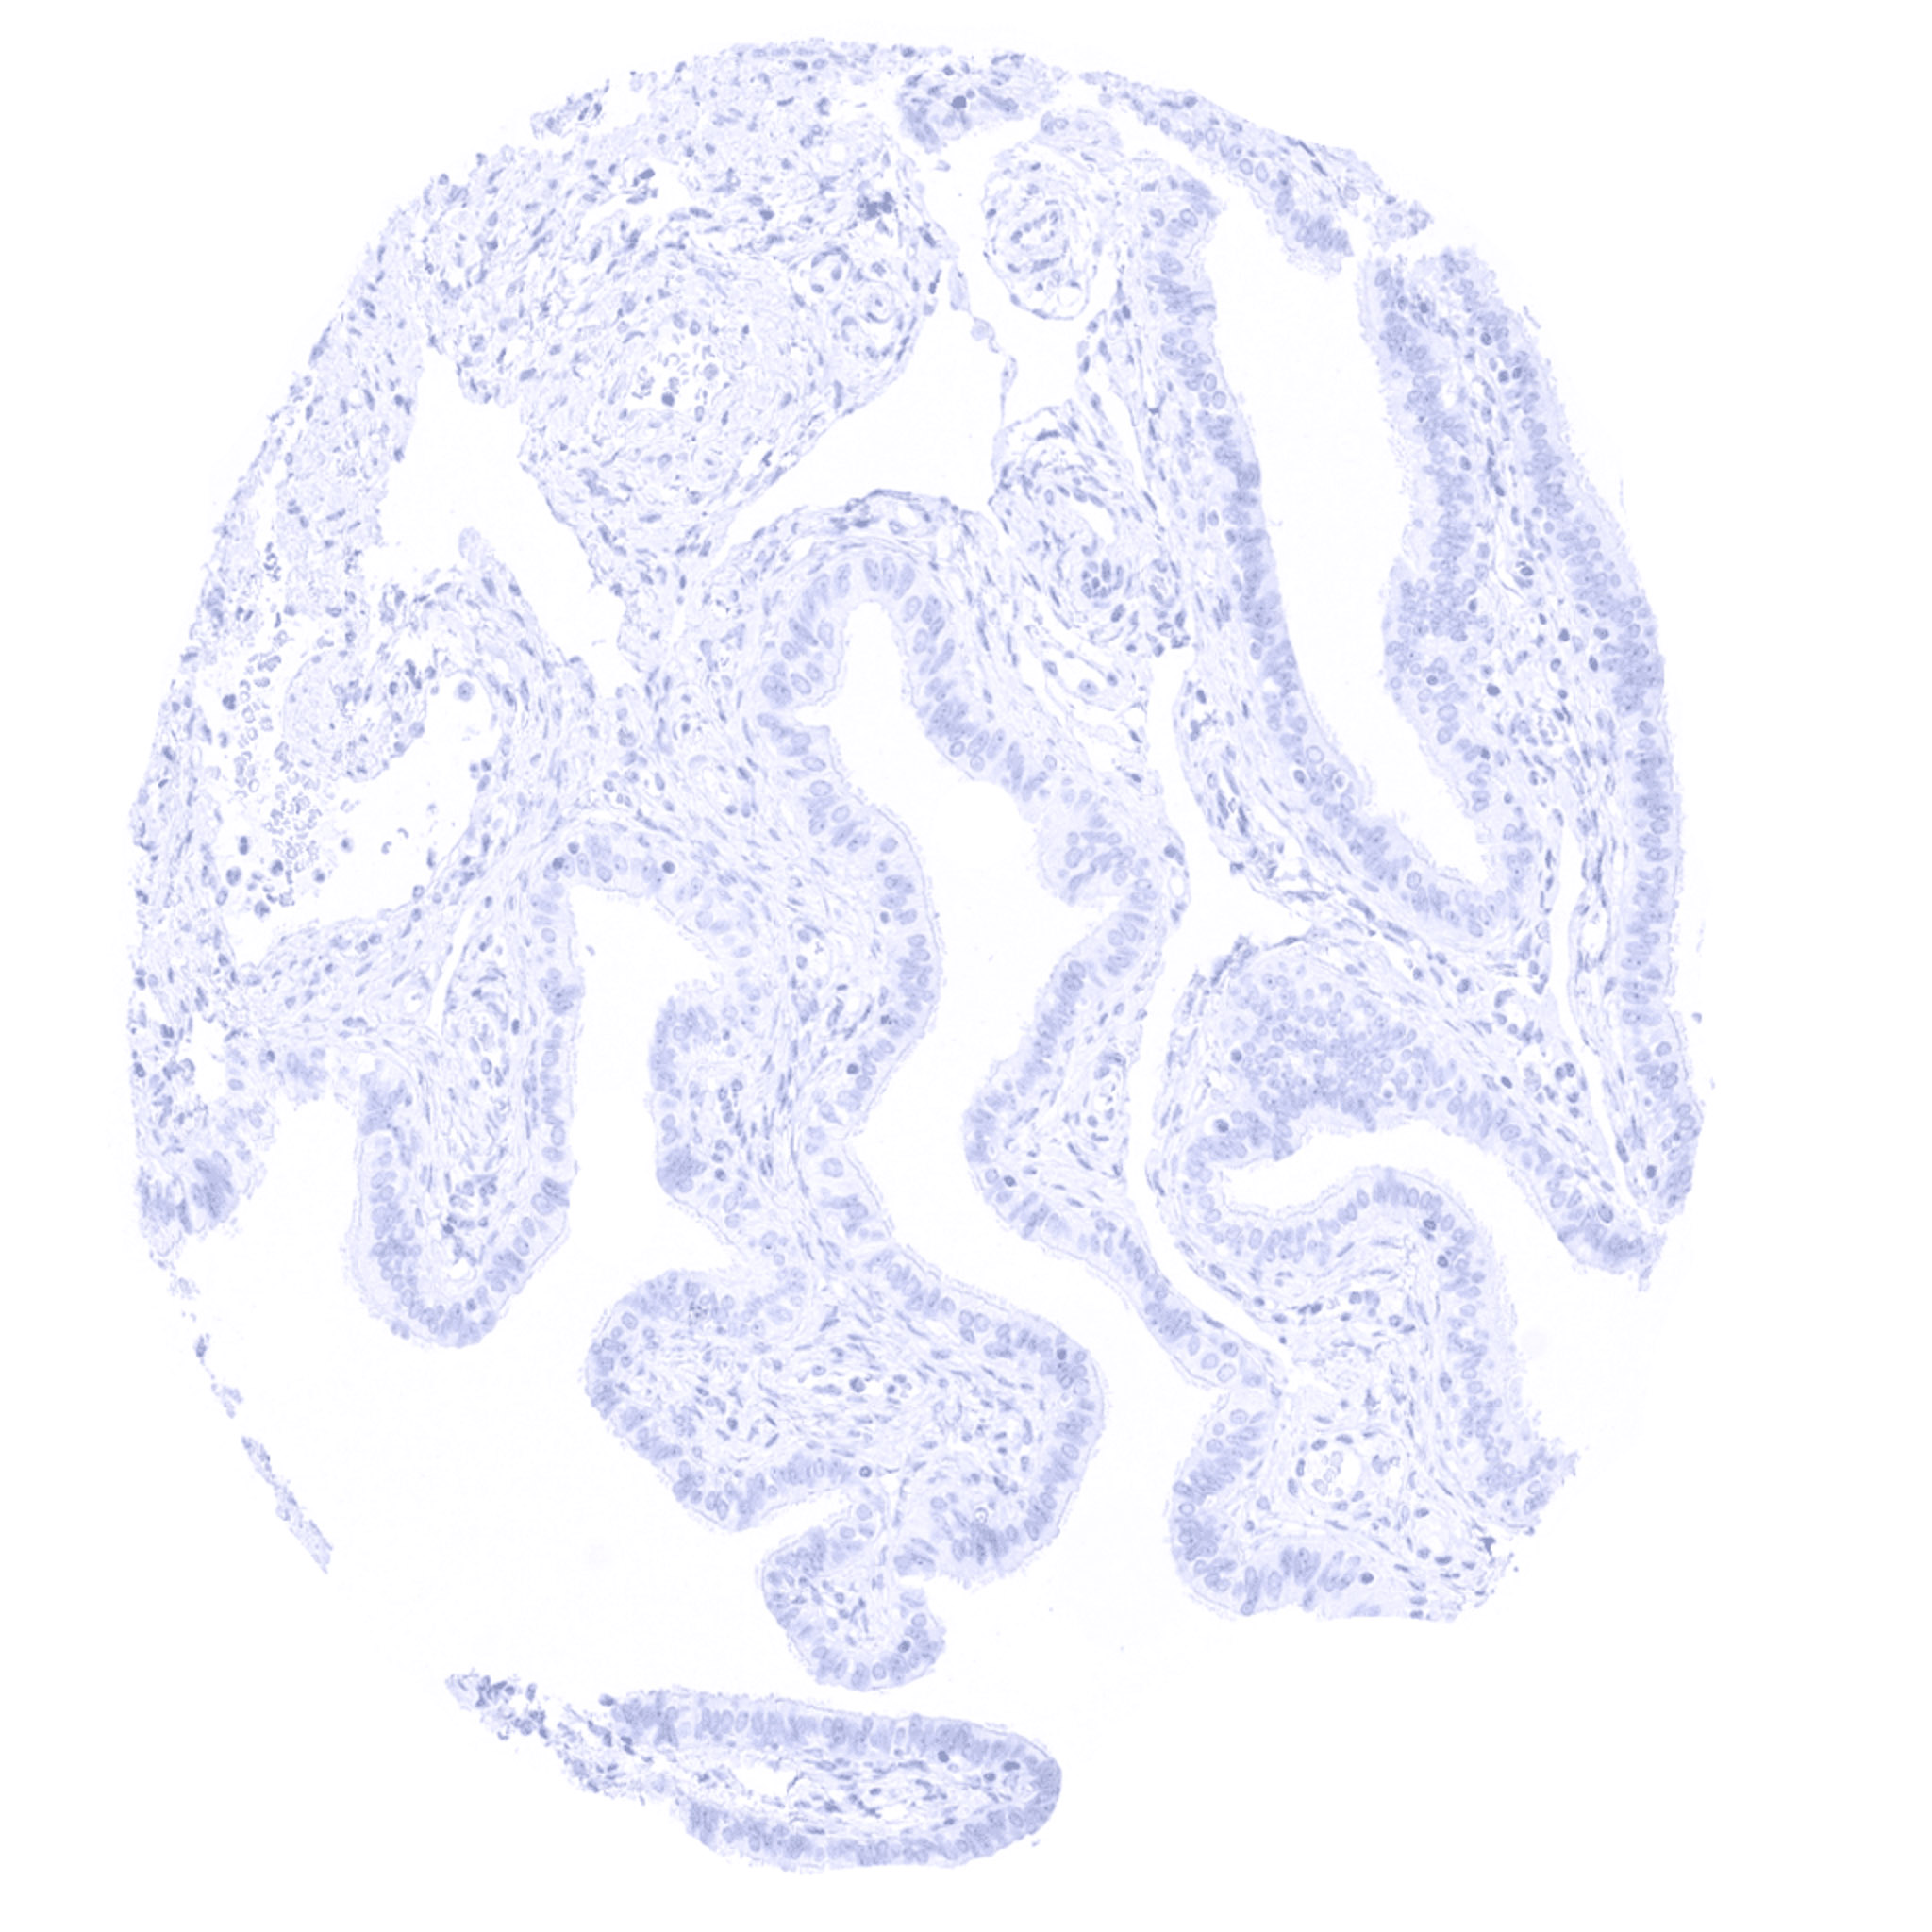

Parathyroid – Parathyroid gland showing intense cytoplasmic Parathyroid Hormone immunostaining of all glandular cells.

Parathyroid – Strong cytoplasmic Parathyroid Hormone immunostaining of all cells of a parathyroid gland.